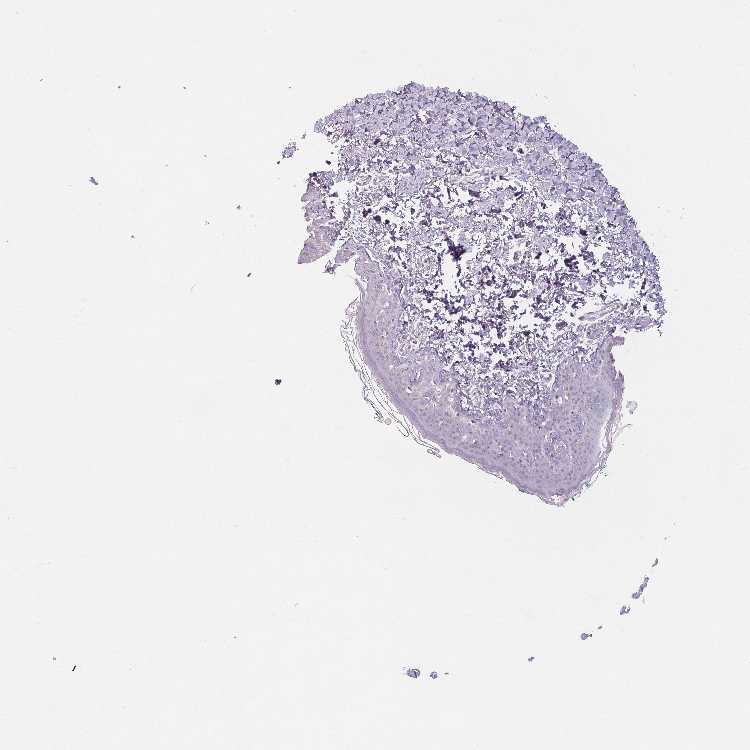

SKIN 1 - Antibody stainingi

Antibody staining in the annotated cell types in the current human tissue is reported as not detected, low, medium, or high, based on conventional immunohistochemistry profiling in selected tissues. This score is based on the combination of the staining intensity and fraction of stained cells.

Each image is clickable and will lead to virtual microscopy that enables deeper exploration of all samples and also displays staining intensity scores, fraction scores and subcellular localization as well as patient and tissue information for each sample.

Antibody HPA037366Antibody HPA050388Antibody CAB032654

Langerhans -Not detectedLow

Cells in basal layer Medium--

Cells in corneal layer Not detected--

Cells in granular layer Medium--

Cells in spinous layer Medium--

Endothelial cells Low--

Extracellular matrix Not detected--

Fibroblasts -Not detectedNot detected

Fibrohistiocytic cells Not detected--

Hair follicles Medium--

Keratinocytes -Not detectedLow

Langerhans cells Medium--

Lymphocytes Medium--

Melanocytes Not detectedNot detectedLow

Sebaceous glands Medium--

Vascular mural cells Not detected--